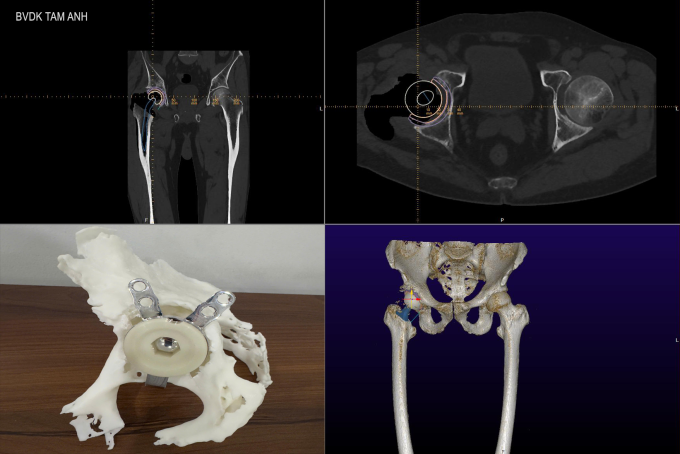

Sau hội chẩn, các bác sĩ sử dụng đồng thời nhiều công nghệ 3D tiên tiến để chuẩn bị cho cuộc mổ. Bác sĩ chỉ định chụp CT 3D hơn 100.000 lát cắt để tạo ra hình ảnh ba chiều chi tiết của khớp háng, quan sát toàn diện cấu trúc xương khớp và phát hiện các tổn thương tiềm ẩn. Với công nghệ này, liều xạ của mỗi lần chụp rất thấp, chỉ bằng một lần chụp X-quang nhưng vẫn cho ra được hình ảnh xương hoàn chỉnh, hỗ trợ chẩn đoán và điều trị.

Kế tiếp, bác sĩ sử dụng đồng thời hai phần mềm chuyên dụng trong phẫu thuật chỉnh hình là TraumaCAD và MediCAD 3D để tăng độ chính xác khi lựa chọn khớp háng nhân tạo. TraumaCAD phân tích cấu trúc khớp dựa trên hình ảnh X-quang, còn MediCAD 3D lập kế hoạch phẫu thuật dựa trên dữ liệu hình ảnh 3D từ phim CT. Các phần mềm này cho phép bác sĩ định vị chi tiết cấu trúc giải phẫu, tính toán được độ nghiêng của ổ cối, hướng đặt khớp háng nhân tạo, mô phỏng chuyển động khớp... Từ đó, bác sĩ lựa chọn khớp phù hợp với cơ thể người bệnh và lên kế hoạch phẫu thuật với độ chính xác cao.

Bác sĩ Khoa tiến hành phẫu thuật "ảo" thử nghiệm, sử dụng công nghệ in 3D tạo ra mô hình khớp háng với kích thước 1:1 như khớp thật, giúp dự trù được các tình huống có thể xảy ra khi mổ và có kế hoạch xử lý nhanh chóng, rút ngắn thời gian phẫu thuật thực tế.